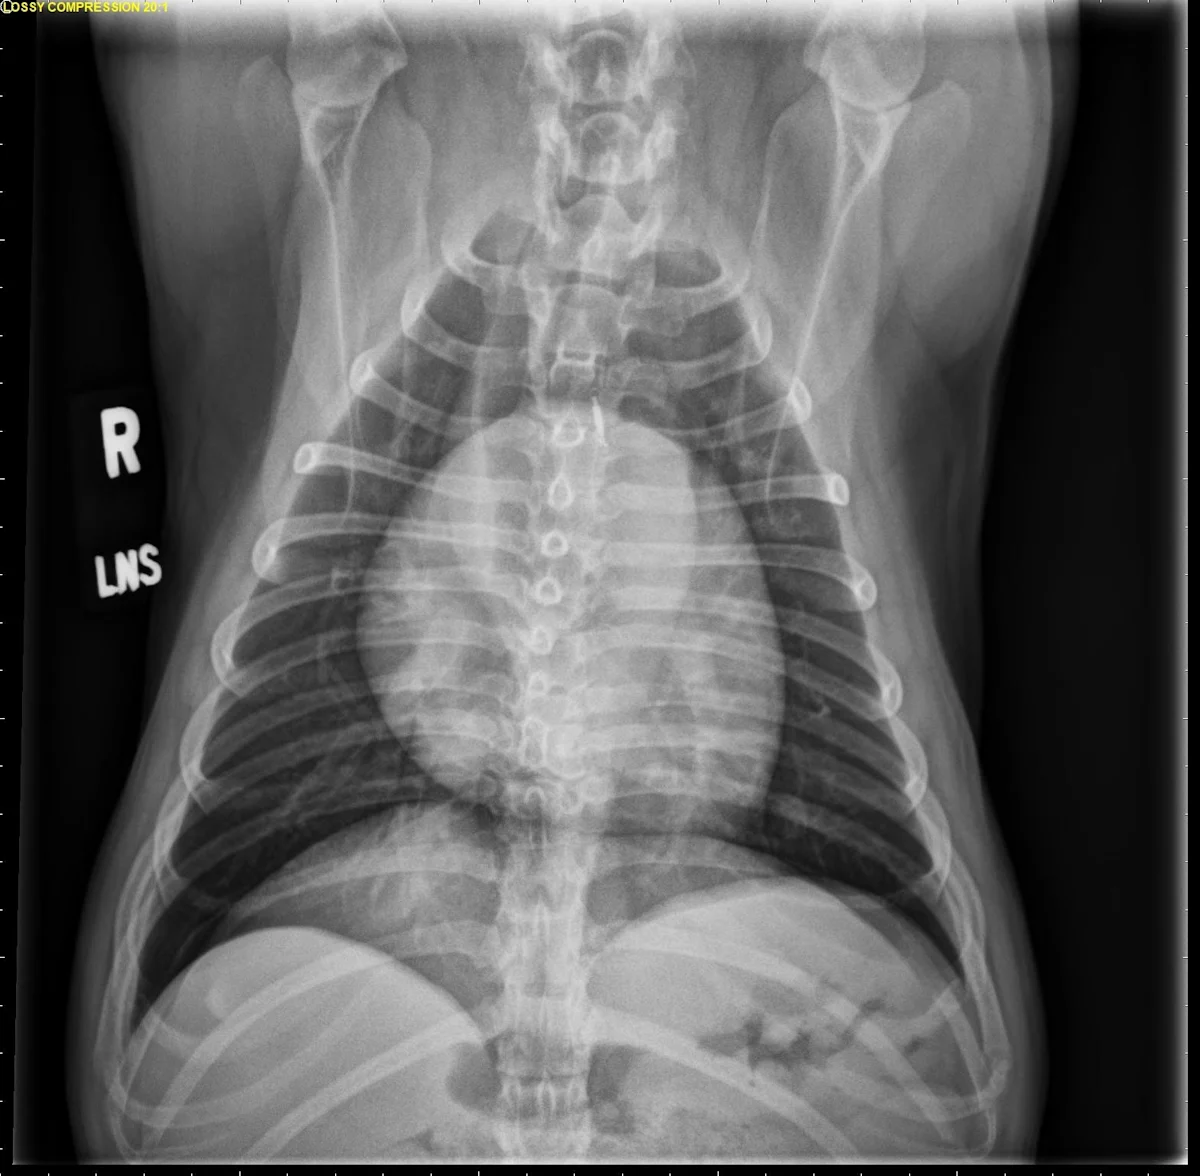

FIGURE 2 Normal DV (left) and VD (right) projections of the thorax in a large, crossbreed dog. The cardiac silhouette appears more rounded, and the caudal pulmonary vasculature is more apparent (arrowheads) in the DV view compared with the VD view. In some DV projections, the cardiac silhouette can appear significantly displaced to the left (not apparent in this case). Images courtesy of Federico Villaplana Grosso, DACVR, DECVR